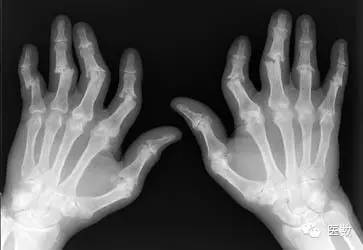

炎症性疾病:类风湿性关节炎、强直性脊柱炎

【类风湿性关节炎】